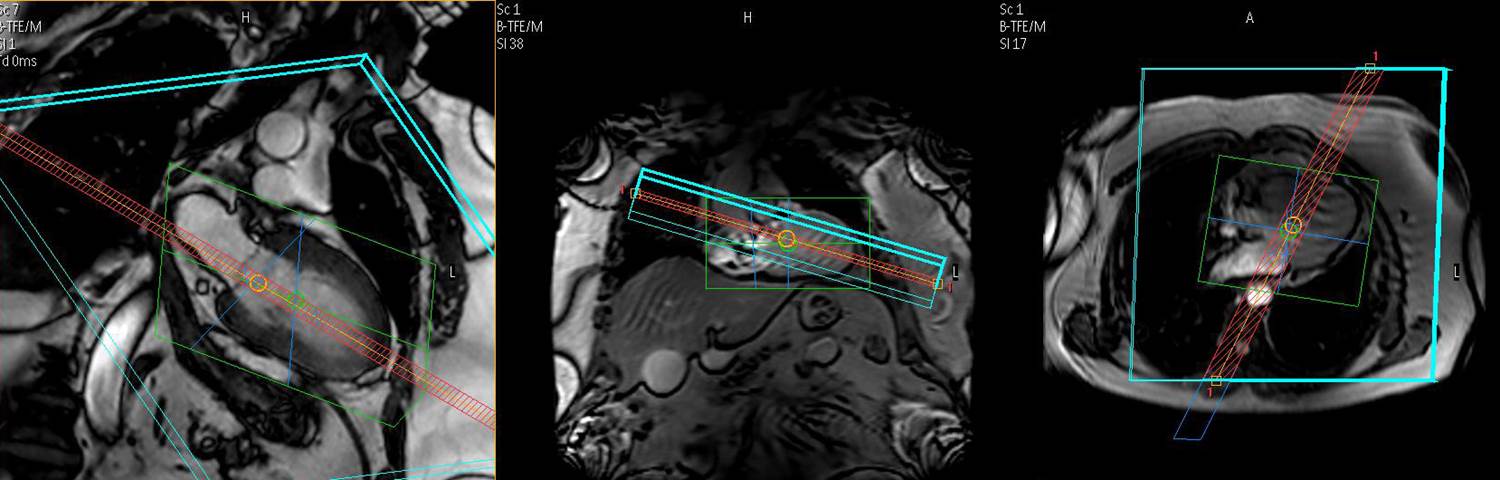

This workshop offers dedicated training on the principles and applications for quantitative tissue characterization using T1, T2, and T2* mapping techniques.

The course focuses on advantages and limitations of novel pulse sequences for parametric mapping and their clinical applications for assessing fibrotic, inflammatory and infiltrative cardiomyopathies, myocardial edema and iron overload.